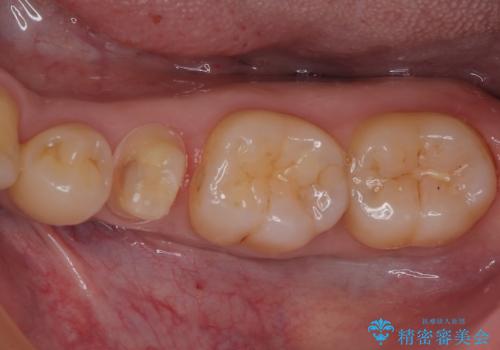

- 左下の奥歯のところがフロスが引っかかったり、ちぎれたりするとのことで来院された患者様です。検査の結果、神経は正常な反応を示し、フロスは引っかかる状態でしたので、虫歯治療も併せて行うためにオールセラミッククラウンによる補綴治療を行っていくことにしました。

拡大鏡視野下でプラスチックの詰め物、虫歯を除去しオールセラミッククラウンに適した形に整えました。

歯と歯茎の間に圧排糸と言われる糸を入れてシリコーン印象材にて型どりをしました。